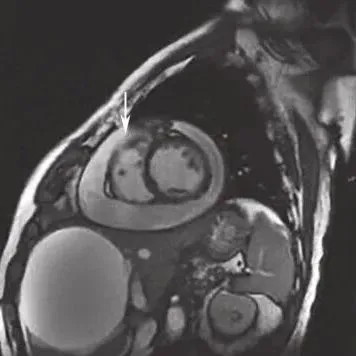

静息状态下可见左室前间壁心尖段、室间隔及左室前壁心尖段室壁变薄(约4mm),回声偏低,运动明显减弱;心包检查可见中-大量液性暗区包绕心脏,心脏呈“摆动征”;右房、右室受压变小(图3)。

图3入院时超声心动图

左室前壁右室梗死的超声心动图特征为于心尖四腔心切面显示室间隔心尖段运动异常,并延续至右室心尖部,可累及右室游离壁近心尖区。右室心尖部运动异常区呈正三角形,宽底在右室心尖1/3处,梗死顶部指向心底部。右室游离壁破裂的超声心动图表现为:①右室游离壁破口对应的心包腔内可见不同程度的液性暗区;心包腔内液性暗区迅速增宽为心脏压塞的特征性图像改变,彩色多普勒于相应切面可见心包腔内液性暗区中红或蓝色血流束,由穿孔处至心包腔;②穿孔的室壁可于相应心腔切面上呈现心室壁回声中断;穿孔部位的心肌较薄且运动失常;③由于心包腔内压力增高,心室收缩力减弱,穿孔处的血流速度多较低。心肌破裂处无论位于前壁或下壁,均为纵行裂口,表层裂口较大,里层较小,常常形成迂曲不整的孔道。由于右室解剖形态的特殊性,并受常规心脏超声切面观察角度的局限,本例患者多次超声检查均未能明确破口位置,是诊断困难的原因之一。心包积液临床症状的发生主要是由于大量心包积液压迫心脏和周围器官及组织所引起,取决于心包腔内的液体量、液体蓄积增加的速度和心包的特征。当心包腔内液体量缓慢增加时,有一定弹性的心包被扩展以接受所增加的液体量,而心包腔内压力几乎不变。在此情况下,心包腔内液体蓄积可达2000ml而不引起心包腔内压力升高。相反,若心包腔内液体量增加迅速,即使200ml也可引起心包腔内压力急剧升高,使心脏受压而产生血流动力学变化。本例患者第一次心包穿刺引流量为560ml,此后间隔2~3个月定期复查并先后行4次心包穿刺,引流量分别为1370ml、590ml、920ml、970ml,性质相同,均为血性心包积液。曾反复行肿瘤、结核及其他病原学相关检查,未见阳性发现。考虑存在超声无法探明的心肌梗死后心肌微小破裂,保守治疗未能正常愈合,致血液持续渗出心包腔,为了证实这一推论,又对患者进行了心肌声学造影及增强磁共振成像,结果示心肌声学造影无异常发现,增强磁共振成像可见存在心包腔至心室方向的湍流信号,提示心肌微小裂孔的可能。因右室压力显著低于左室,渗液速度缓慢,故未引起急性心脏压塞症状,是临床诊断的干扰因素,也是患者得以幸存的原因。